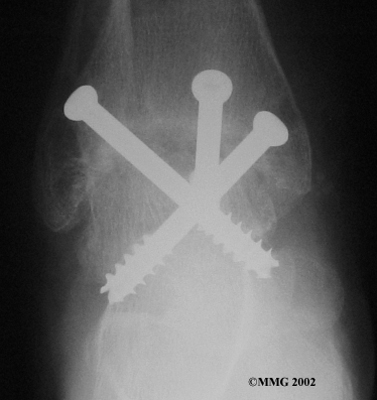

Ankle Fusion

When the ankle joint becomes so painful that it is difficult to walk, surgery may be suggested to fuse the ankle joint. An ankle fusion is sometimes also called an ankle arthrodesis. In this operation, the three bones that make up the ankle joint (the talus, the tibia, and the fibula) are allowed to grow together, or fuse, into one bone. Once this is done the ankle no longer is able to move, but with a successful fusion the pain is gone. Most people with a successful fusion of the ankle are able to walk without much trouble, and in some cases it is almost impossible to tell that the ankle is stiff. But it is very difficult to run because you lose the ability to push off with the toes. The foot can't bend down.

Most people will need some changes made to their shoes following an ankle fusion. Because the ankle no longer moves, it is difficult to roll over the top of the foot when you take a step. For this reason, shoes are usually fitted with a rocker sole. This allows the shoe to roll instead of the foot. A special heel is sometimes built on the shoe to absorb some of the shock.

The ankle fusion is a good operation, especially for a young, active person. It is usually the preferred option for post-traumatic arthritis of the ankle. Once the ankle is successfully fused it can last a lifetime, and no other operations are expected later unless there are problems. But there are complications associated with the ankle fusion, and not all ankle fusions are successful.

Related Document: FYZICAL Metairie's Guide to Ankle Fusion